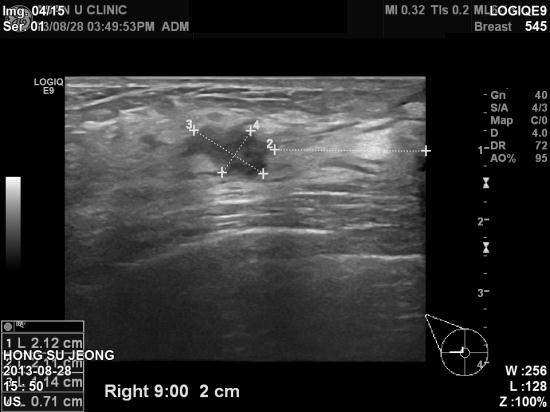

올해 공단검진에서 시행한 유방촬영상 이상소견으로

본원에 의뢰된 만48세 여자분이십니다.

우측 유방에 두개의 혹이 인접하여 있어 조직검사를 실시하여

두군데 다 유방에 잘 생기는 침윤성 유관암이 진단되셨습니다.